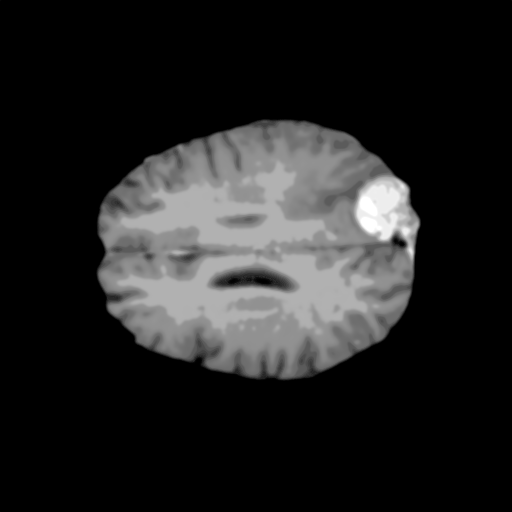

Extensive experiments have been performed in the current setup, and experimental outcomes are reported with the demonstration of numerical and statistical analyses using the proposed QFS-Net, QIS-Net [39], convolutional U-Net [18] and Residual U-Net (URes-Net) architectures [20]. The human expert segmented skull-tripped contrast enhanced DSC brain MR input image slices of size and ROIs are provided in Figure 5 as samples. The demonstration of QFS-Net segmented images followed by the essential post-processed outcome on the slice no. for class level with four distinct activation schemes () are shown in Figure 6. It is evident from the experimental data provided in Table LABEL:tab1 that the proposed QFS-Net performs optimally for the -connected quantum fuzzy pixel information heterogeneity assisted activation () with and gray scale set in comparison with other thresholding schemes and gray scale sets under the four evaluation parameters () [44]. The segmented tumors obtained using the proposed self-supervised procedure under class transition levels with four different thresholding schemes , , and are demonstrated in Figures 7- 8 for the class boundary sets and [39], respectively. The segmented images using the remaining two class boundary sets ( and ) [39] are provided in the supplementary materials section. The segmented ROIs describing the whole tumor region after the masking procedure using QIS-Net, U-Net and URes-Net are also reported in Figure 9.